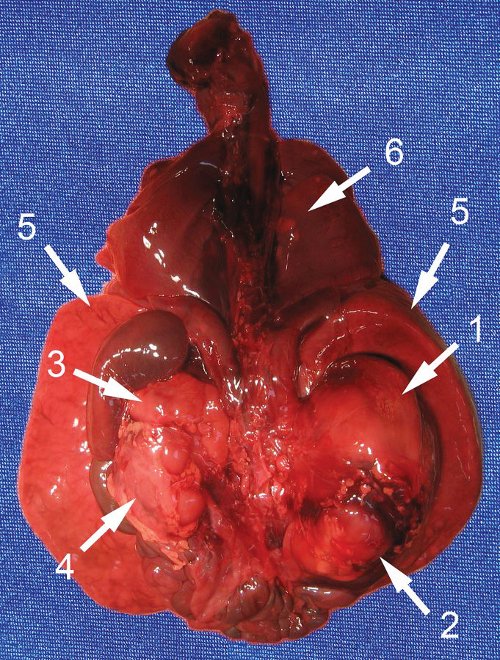

Таким образом, обнаруженное нами образование было отнесено к опухоли надпочечника даже при отсутствии классической картины нейробластомы. Обращали на себя внимание большой размер опухоли и отсутствие выраженных осложнений в виде многоводия, застойной сердечной недостаточности, нарушения фето-плацентарного кровотока. При этом относительно ранняя манифестация (выявление данного комплекса изменений уже в 31 нед), не совсем типичная ультразвуковая морфология опухоли, наличие выраженной гепатомегалии и множественных метастазов позволяли сделать вывод о злокачественном течении заболевания, что, видимо, и обусловило антенатальную гибель плода. В итоге диагноз был подтвержден патоморфологическим исследованием. У недоношенного плода мужского пола живот увеличен в объеме. Справа в забрюшинном пространстве определяется округлое образование (опухоль) размером 50?35?30 мм, эластичной консистенции. Спереди и снизу к опухоли прилежит почка, плотно с ней спаянная. Опухоль исходит из правого надпочечника, который находится на ее верхнем полюсе в виде "шапочки". На разрезе опухоль однородная, желтовато-серая. Левые надпочечники и почка обычного вида. Печень значительно увеличена, занимает около 1/2 объема брюшной полости, доли четко не дифференцируются. Поверхность печени коричневато-красная. На разрезах определяются множественные плотные эластичные узлы диаметром до 15 мм бледно-желтого цвета (рис. 4, 5).

Рис. 5. Органокомплекс, вид сзади.

1 - опухоль с правым надпочечником;

2 - правая почка;

3 - левый надпочечник;

4 - левая почка;

5 - печень;

6 - метастазы в легкие.

На висцеральной плевре определяются множественные очажки желтого цвета диаметром до 4 мм, толщиной менее 1 мм. Ткань легких безвоздушная, дряблая, без видимых очаговых изменений.